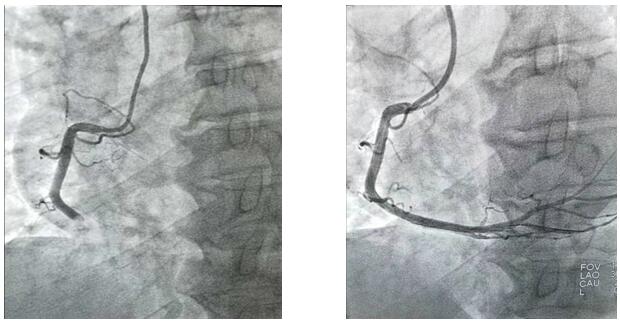

2019年10月1日凌晨1點左右,興平市人民醫(yī)院將一位急性心梗病人送至我院,患者胸痛5小時并伴有大汗,心電圖顯示ST段呈弓背向上型抬高,出現(xiàn)寬而深的Q波和T波倒置。心肌酶及肌鈣蛋白升高。心血管病院值班二線立即通知導(dǎo)管室值班醫(yī)生?!皩?dǎo)管室已啟動”,一場與死神的博弈即將開始,醫(yī)護(hù)人員“飛毛腿”式趕到導(dǎo)管室,護(hù)士開始了準(zhǔn)備工作,“液體已配好、除顫儀處于備用狀態(tài)、急救藥品準(zhǔn)備完畢”的同時,隨著技師“趕快帶病人”。醫(yī)護(hù)人員穿上近30斤重的鉛衣、洗手、戴口罩,一場沒有硝煙的戰(zhàn)爭正式開始了,消毒、穿刺、造影.....手術(shù)緊張而有序的進(jìn)行著,經(jīng)過一小時左右的奮力搶救,病人終于脫離了危險。安全送至CCU后,醫(yī)護(hù)人員此時已經(jīng)筋疲力盡,身上的衣服也已經(jīng)濕透,但大家還是會共同探討手術(shù)的過程。

凌晨3點,手術(shù)室終末消毒工作剛剛結(jié)束,“滴滴滴……”胸痛中心來電,啟動導(dǎo)管室,醫(yī)護(hù)人員再次穿上鉛衣沖向?qū)儆谧约旱奶厥鈶?zhàn)場……10月1日、10月2日、10月3日、10月4日、10月5日、10月6日,我們完成PTCA支架置入術(shù)、冠狀動脈內(nèi)溶栓術(shù)、PTCA腔內(nèi)成型術(shù)、臨時起搏器置入術(shù)、冠狀動脈內(nèi)左室造影術(shù)及冠狀動脈內(nèi)血管造影術(shù)共計心臟介入手術(shù)35例。我們永不停息的穿梭與手術(shù)間,平凡的本職工作中,與死神賽跑.....挽救了無數(shù)名生死垂危的患者,解除患者病痛的同時,還您一個完整、幸福的家!